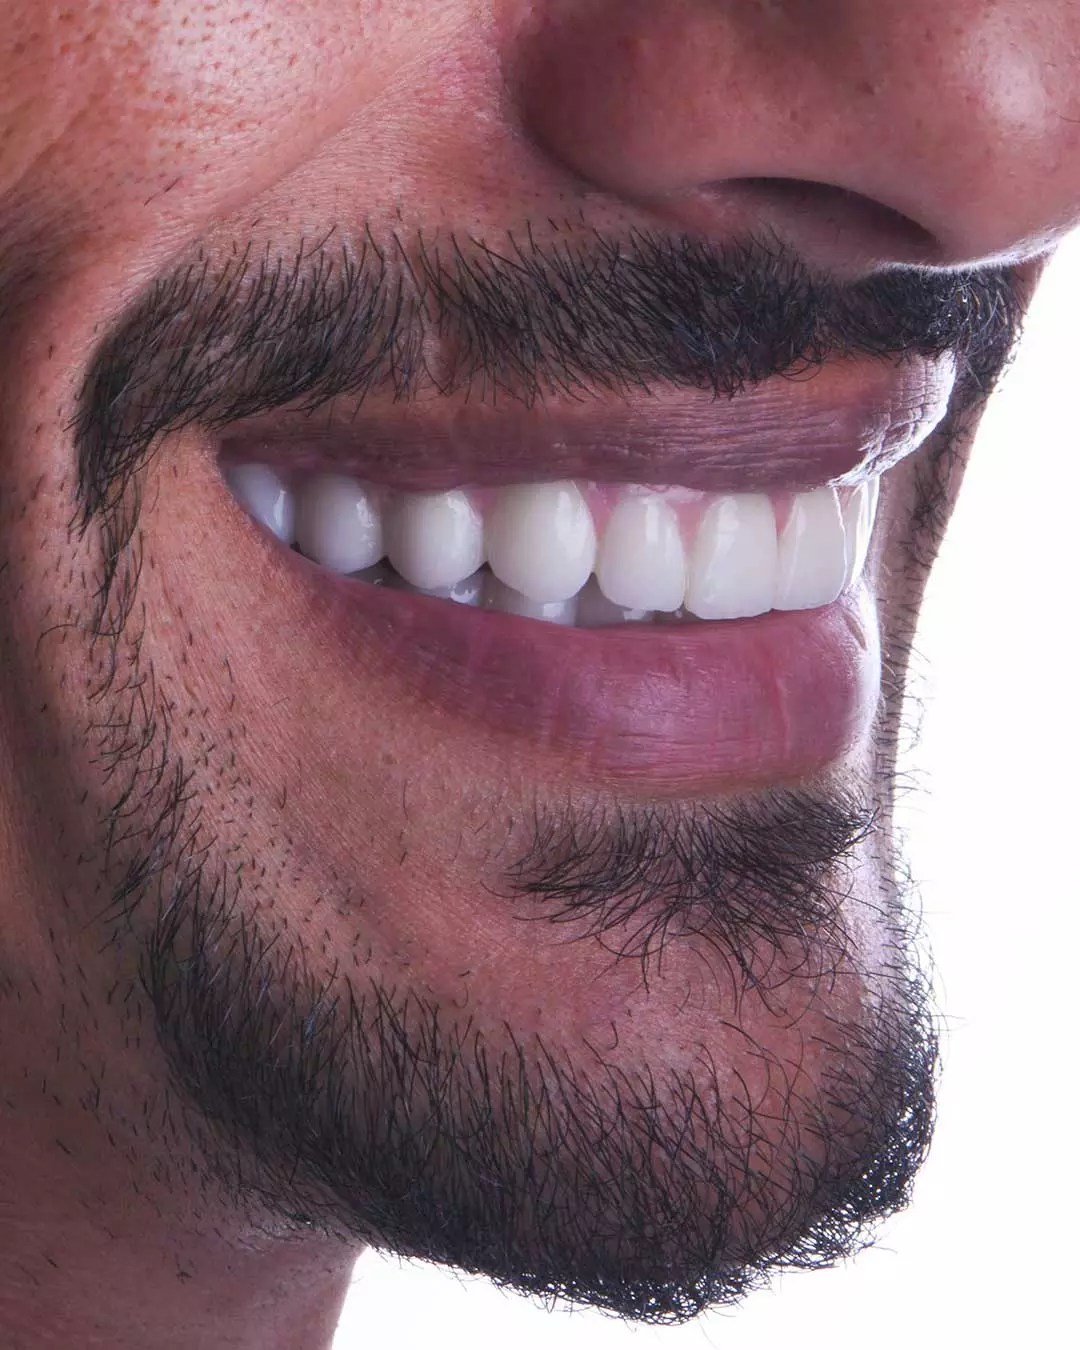

- تبييض الأسنان

- طب الأسنان التجميلي

- عدسات الأسنان التجميلية

- عدسات البورسلان